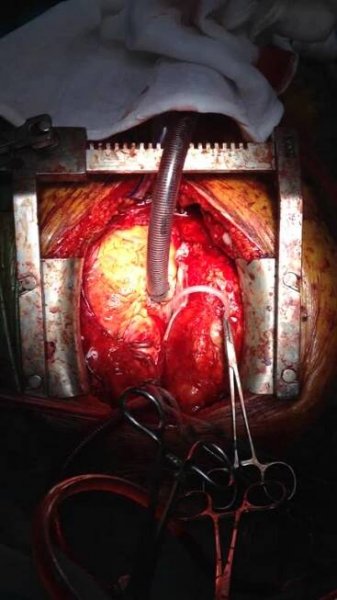

Operační přístup pro MIDCAB

Výsledný stav (napojení mamární tepny věnčitou tepnu) miniinvazivním přístupem na bijícím srdci (MIDCAB)